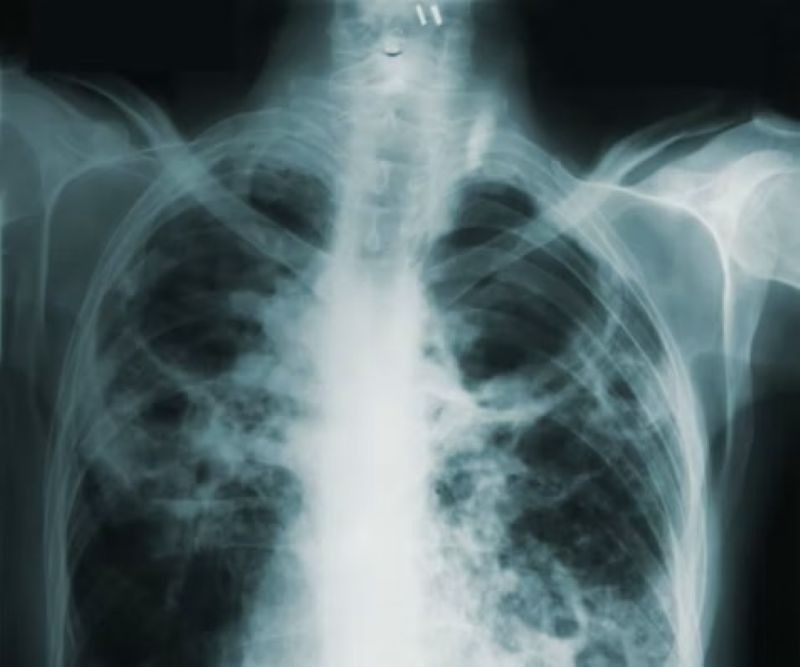

TB

TB is caused by bacteria that most often affects the lungs. Every day, over 3,300 people die from the disease, with Southeast Asia accounting for nearly 40 per cent of deaths. Yet it is both preventable and treatable, including by using the antibiotic rifampicin.